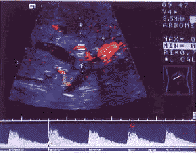

手术前判定肝门部胆管癌根治性切除的可能性时,需要了解肿瘤与肝门重要血管间的关系,在声像图上,由于门静脉内径宽,管壁回声强,通过彩色多普勒极易观察门静脉主干及左右分支,因而较易显示门静脉与肿瘤之间的关系。本组判定肿瘤与门静脉关系并与手术对照,手术证实4例受侵,2例未受侵,出现了1例假阴性,无假阳性,诊断符合率为 83.3%,与文献报道[1,3]的 81.0%~86.0%相近。4例门静脉受侵病例表现为:1例门静脉左支完全阻塞,未显示彩色血流;2例显示门静脉左支或右支内径变细,流速加快,高达60 cm/s以上(图4);另1例彩超显示门静脉右前支内径 3.6 mm,流速为 27 cm/s,术前诊断门静脉未受侵,手术证实门静脉右前支管壁受浸润。在11.0%~40.0%胆管癌患者,门静脉受侵表现为频谱增宽、流速加快,只有当血管狭窄超过 70.0%时,多普勒频谱才会发生变化[4,5]。在观察肝门部胆管肿瘤与门静脉之间关系时,应从以下4个方面综合考虑:①血管与肿瘤之间的回声界面;②血管壁的回声界面;③血管的外形,有无局部狭窄或扩张;④血流流速及频谱曲线。

图4 门静脉受侵:管腔变细、流速增快